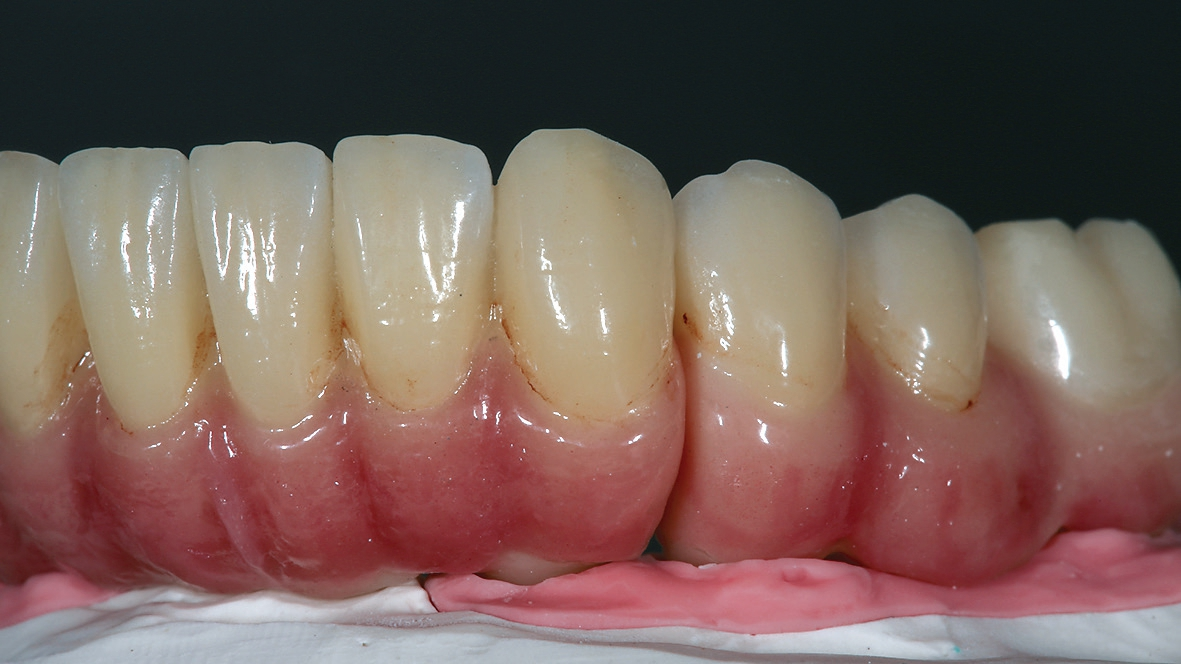

Bei reizlosem postoperativem Verlauf konnten die Implantate wie geplant nach drei Monaten freigelegt werden. Um das Emergenzprofil für die Prothetik möglichst optimal zu gestalten, kamen dabei sowohl zylindrische als auch wide body Gingivaformer zum Einsatz. Nach einer Heilungszeit von zwei Wochen für das Weichgewebe wurde der Patient für die prothetische Phase an die zuweisende Zahnarztpraxis (Dr. Andreas Karg, Lenggries) zurücküberwiesen. Dort wurde der Unterkiefer mit drei Brückensegmenten 46-44, 43-33, 34-46 definitiv versorgt. Zunächst erfolgte nochmals eine exakte zentrische Relationsbestimmung mit auf den Implantaten verschraubten Gerber-Stützstiftregistrat-Platten (Abb. 16). Anschließend wurden die Brückengerüste in CAD/CAM-Technik konstruiert und aus Zirkonoxid gefräst und individuell keramisch vollverblendet. Im Oberkiefer wurde zunächst ein auf provisorischen Abutments reversibel zementiertes Langzeitprovisorium aus PMMA mit glasfaserverstärkten Strängen (Targis Vectris) eingegliedert, um Phonetik, Ästhetik, Hygienefähigkeit und die Bisslage nochmals über eine Tragezeit von sechs bis neun Monaten zu evaluieren und falls notwendig letzte Korrekturen durchführen zu können (Abb.17-23). Danach ist die definitive Versorgung mit vier einzelnen Brückensegmenten in regio 16- 14, 13-11, 21-23 sowie 24-26 geplant.